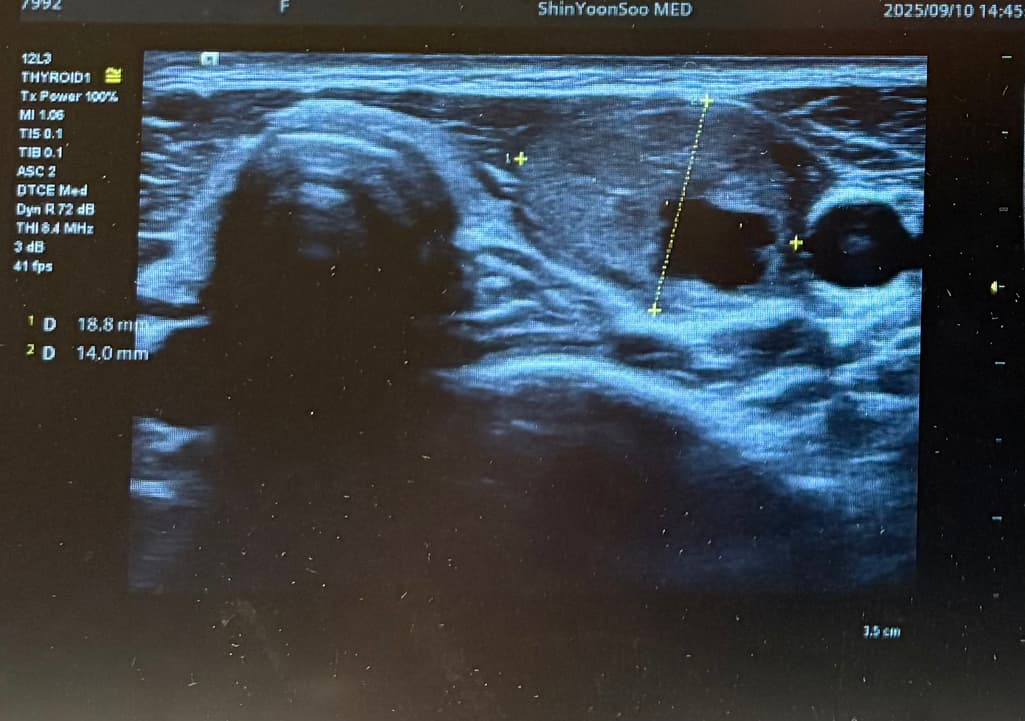

Lt 1ower lobe

1.88x1.4x2.84cm mixed nodule Lt middle lobe 1.22x0.37x 0. 49cm의 nodule 소견으로(의뢰서에 적혀있던 내용) 초진 보러가니 초음파 사진만 보시고는 식도와 신경에 들러붙어있고 점점점 커지면서 추후엔 응급수술로 진행될 수 있으니 아직 젊을때 빠르게 수술로 떼어내자고 결론은 수술밖에 없다고 냅다 수술일정 한달뒤로 잡고왔습니다.

왼쪽에 약 3cm가량으로 전체가 혹일거라며 상황이 많이 안좋은거고 위치가 안좋다고 하셔서 다음주에 수술전 검사 받은 후 2주뒤 입원으로 일정이 잡혔는데 보통 세침검사 또는 총생검사 후 수술 여부가 결정되는걸로 알고있는데 ..

위치가 그렇게 안좋은건가요..? 주변에서 어떻게 보면 동맥부근이랑도 붙어있다는것 같이 말하네요..